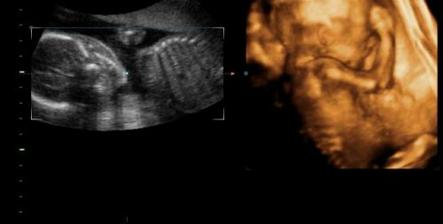

Tak jsme se dočkali!Dne 15.10.2007 nám bylo potvrzeno ultrazvukem těhotenství (5.týden)Na miminko se strašně moc těšíme a doufáme ,že vše bude probíhat tak jak má 🙂.Bereme vitamíny Gravital,osvědčily se nám i u Tomáška 🙂.Za 14 dní jdeme na ultrazvuk,tak se moc těším.Věciček máme hodně,ale samozřejmě budeme nakupovat o to víc pokud to bude holčička ,kterou bychom si mooooc přáli,ale hlavní je abychom byli zdraví 🙂.Dnes tj.28.11.jsem byla na 3D ultrazvuku (12.týden),tak jsem sem přidala nějake foto 🙂.Tak dnes 30.1.2008 jsem byla opět na 3D ultrazvuku (21.týden) a zjistili jsme ,že čekáme holčičku.Tak se nám povedl páreček.S manželem máme velkou radost,protože jsme si holčičku moc přáli 🙂).Tak ve 32.týdnu potvrzena holčička.Zatím vyhrává jméno Valérie.Ve 32.týdnu važíme cca 1924g 🙂).Tomíček se na sestřičku moooooc těší a už teď mi se vším pomáhá.